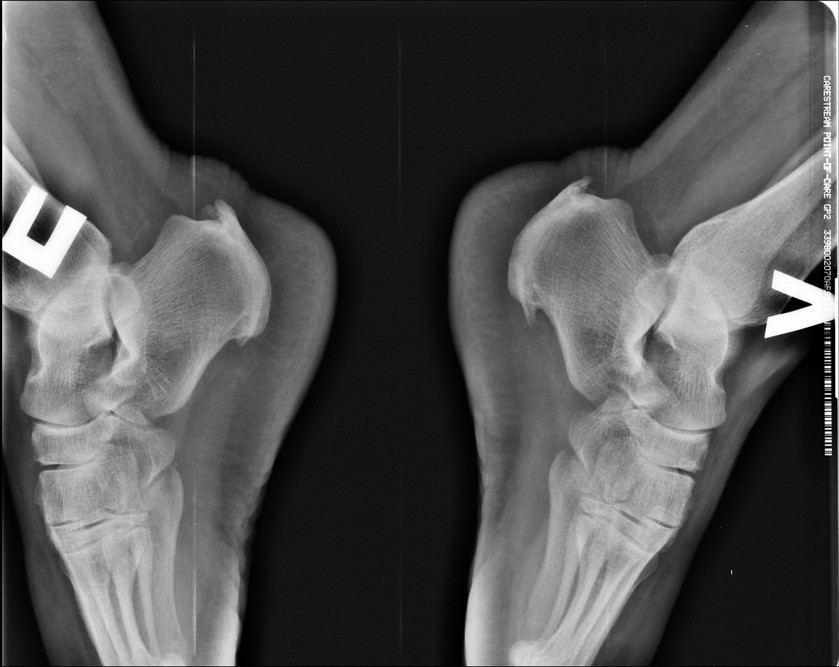

Здравствуйте, коллеги. Пациетка 37 лет, давность заболевания 3 года. Консервативное лечение без эффекта (иммобилизация, НПВС, местное и физиолечение).

Сопутствующее ожирение 3 степени.Снимки прилагаю. МРТ нет. Внешне классическая картина опухолевидных плотных болезненных образований в области прикрепления ахилла. Пунктировал, жидкости не получил.Видимо пора ставить вопрос оперативного лечения, хотел бы услышать ваше мнение, особенно тех, у кого есть такой опыт. Доступ открытый. Спасибо.